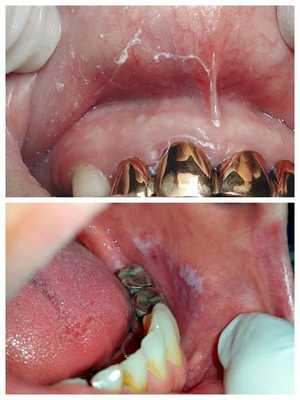

- Слизистая полости рта вестибулярной поверхности бледно-розового цвета, слизистая нёба, язычной поверхности и языка гиперемирована.

Типичная форма гальваноза проявляется наряду с повышением потенциометрических показателей более чем в 3 раза постоянными клиническими проявлениями заболевания - как местными (металлический привкус во рту, жжение, сухость, выявление при стоматологическом осмотре признаков гиперемии слизистой, явлений стоматита, гингивита, лейкоплакии и т. д.), так и общими (слабость, раздражительность, головная боль, снижение работоспособности).

Если металлические включения, вызвавшие появление гальванизма, своевременно не удаляются, в полости рта начинают развиваться воспалительные изменения в виде гингивитов, папиллитов, стоматитов, а также аллергические реакции, связанные с выделением в слюну продуктов коррозии металлов. Гальваноз, сохраняющийся в течение нескольких лет, нередко приводит к появлению лейкоплакии и других предраковых заболеваний слизистой оболочки полости рта, что значительно повышает риск развития злокачественных новообразований в этой области.

Симптомы галь ваноза более выражены в утреннее время. Наиболее часто болезнь сопровождается поражениями слизистых оболочек рта:

- гиперкератозом — утолщением (ороговением) слизистой с появлением на ней белых участков;

- эрозиями и язвами.

Очаги изъязвлений с признаками местного воспаления локализуются в основном на кончике языка или его боковых поверхностях, а также на губах, нёбе, внутренней поверхности щёк [1] [4] [5] [11] .